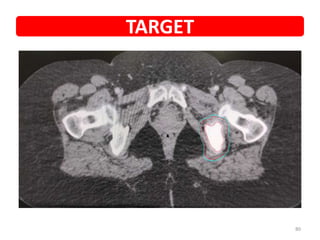

79

Isolated bone mets

TARGET

80

• NAME • UMR •Diagnosis • Metastatic Carcinoma Breast • Presented with • Pain over left hip • PET • Increased tracer uptake is seen in left acetabulum along the posterior margin and the left ischium showing sclerotic changes (SUV max - 6) • Planned SBRT • 33Gy/3# • PET POST SBRT 3M • No definite focal hypermetabolic or abnormally enhancing lesion • Increased sclerotic changes in the lesions noted in left acetabulum, ischium and inferior pubic ramus – s/o complete metabolic response • COURTESY • DR PSB Case details 78

• 79.

• 80.